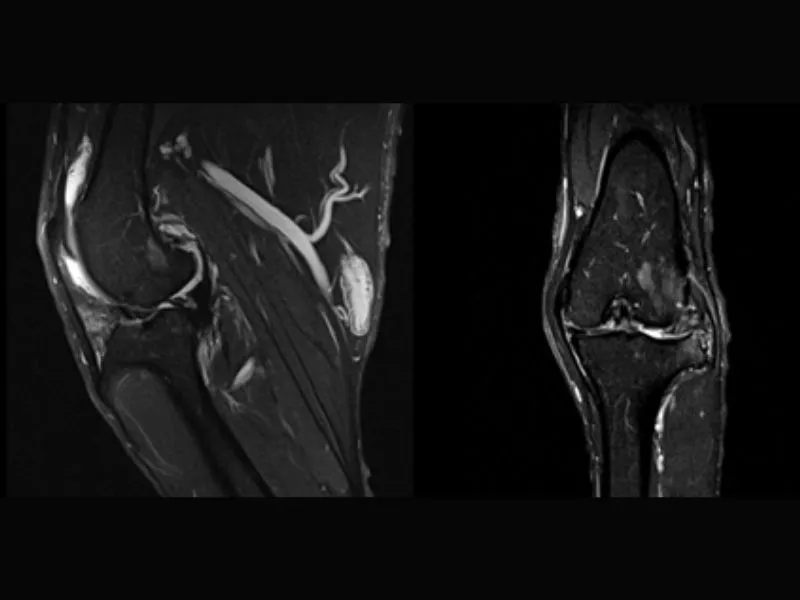

Vet-MR Grande – GE STIR sagittal Dog knee acl fracture

Magnifico Vet – GE STIR Sagittal Stifle